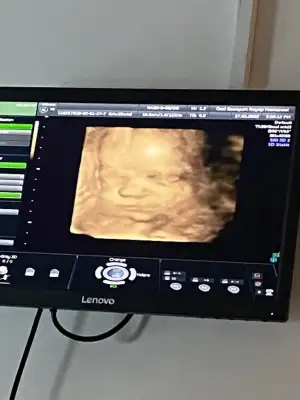

Bugun minik bir kizi ziyaret ettim teyzeleri 😊 Buyumus haftasiyla uyumlu olmus 🤲🏻 29+4 teyiz kilosu 1436, boyu da 38 cm😊

Bu da gul yuzuuu 🥰🥰🧿🧿🧿🧿

Yaaa maşallah benim oğluşumun akranına 🥰 nasıl da narin çıkmış yüzü 😍🧿🧿🧿

Ay maşallah ne güzel çıkmış yerim onu 🧿🧿😍

Masallah tontise çok sevimli çıkmış. Masallah 🧿🧿

Minnoşum ne kadar tatlı cıkmışşşş yerim onu masallahhhh🧿🧿😍😍 her şeyin yolunda olmasına çok sevindim canımm sağlıkla gelsin inşallah😍